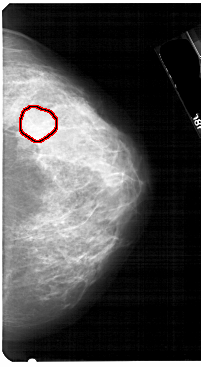

A_1752_1.RIGHT_CC

RIGHT_MLO LINES 5491 PIXELS_PER_LINE 3511 BITS_PER_PIXEL 12 RESOLUTION 43.5 OVERLAY

FILE: A_1752_1.RIGHT_MLO.OVERLAY

TOTAL_ABNORMALITIES 1

ABNORMALITY 1

LESION_TYPE MASS SHAPE LOBULATED MARGINS OBSCURED

ASSESSMENT 4

SUBTLETY 2

PATHOLOGY BENIGN

TOTAL_OUTLINES 1

BOUNDARY